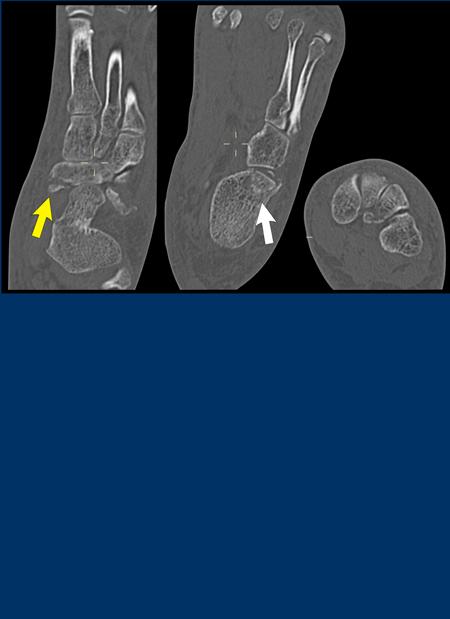

case 4 – distortion

Đây là một trường hợp khác của gãy xương kiểu hạt dẻ do lực nén ở phía bên ngoài của cổ chân do sự lật ngoài ở khớp Chopart.

Sự lật ngoài cũng có thể dẫn đến tổn thương giãn cách ở phía xương sên-thuyền với hoặc là đứt rời gân cơ chày sau hoặc là bong điểm bám của cực trong xương thuyền, nơi gân bám vào, như đã thấy trong trường hợp 2.